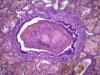

Подскажите как назвать данную пневмонию. По закону парных случаев, на данный момент у меня два разных случая с одинаковой морфологией. В морфологии в альвеолах эозинофильное содержимое, слущенные альвеолоциты, гигантские, многоядерные клетки, выраженный геморрагический компонент, местами немного лейкоцитов, свертки фибрина. Обширные свертки в бронхах. Очень похоже на вирусную, но как ее может назвать морфолог?

Интерстициально-десквамативная.

+ местами похоже на гиалиновые мембраны и в капиллярах межальвеолярных перегородок встречаются мегакариоциты.